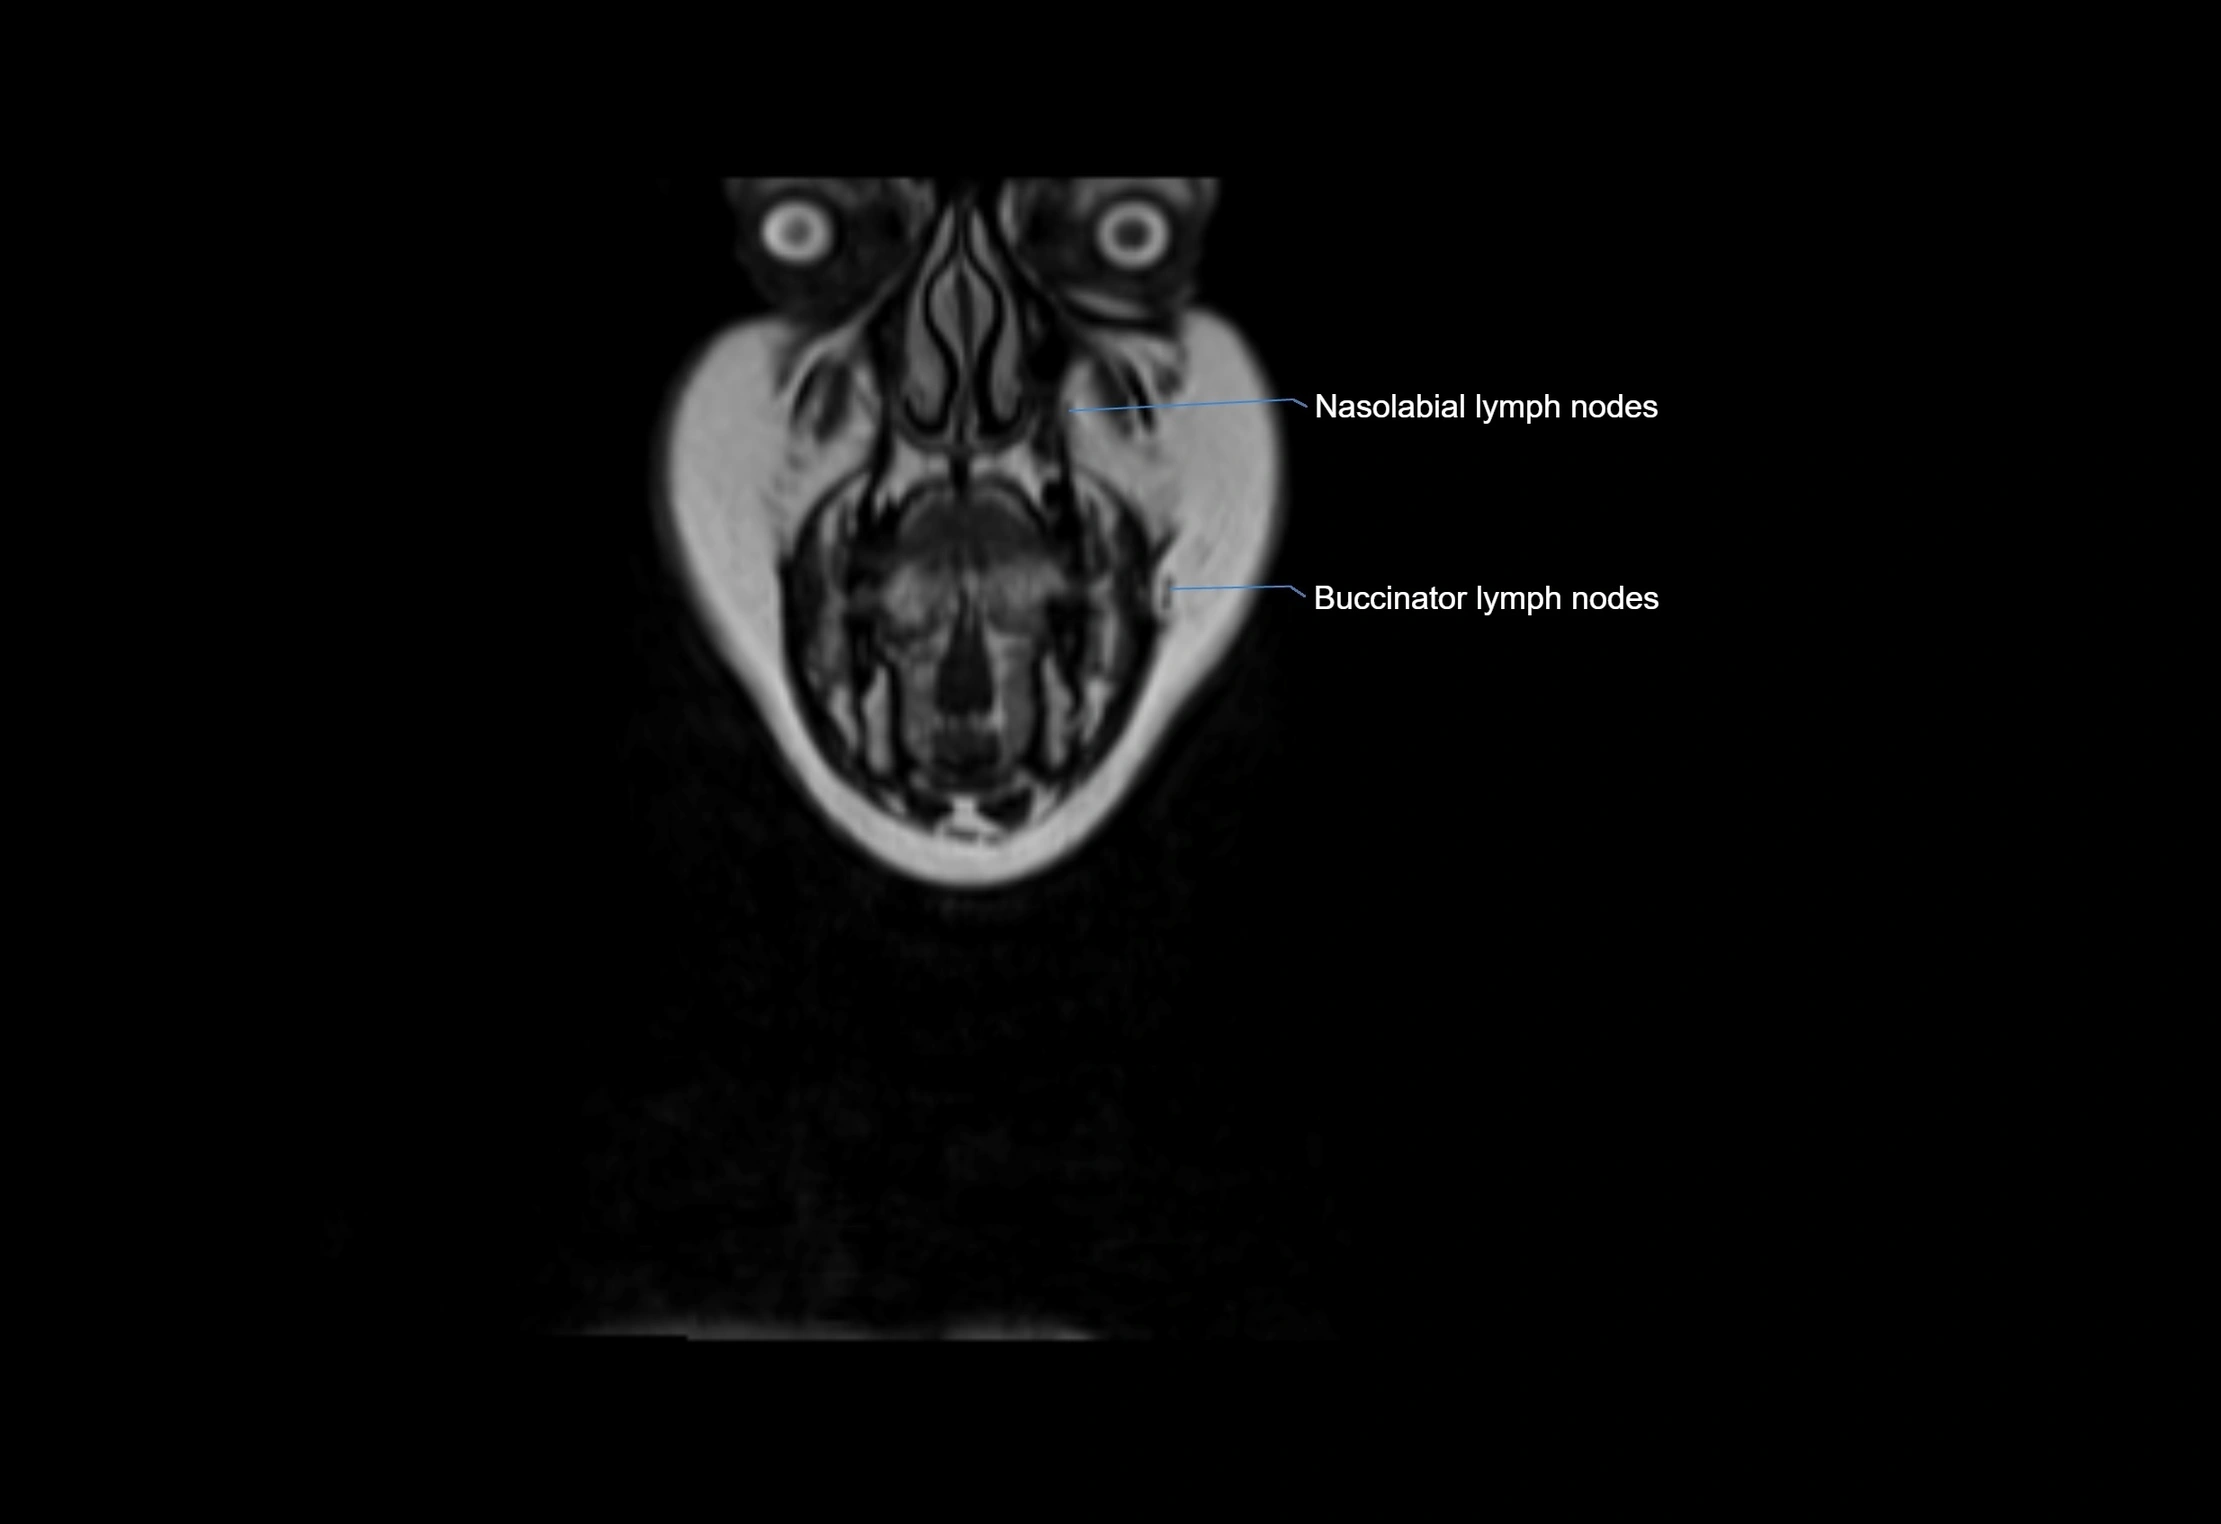

Location

• Found along primary lymph node chains, including preauricular, submandibular, parotid, and occipital regions

• Embedded in subcutaneous fat or superficial fascia, often lateral or posterior to primary nodes

MRI Appearance

T1-weighted images:

• Normal accessory nodes appear as small, oval hypointense to intermediate signal structures within subcutaneous fat

• Surrounded by hyperintense fat, enhancing contrast for visualization

MRI images

image